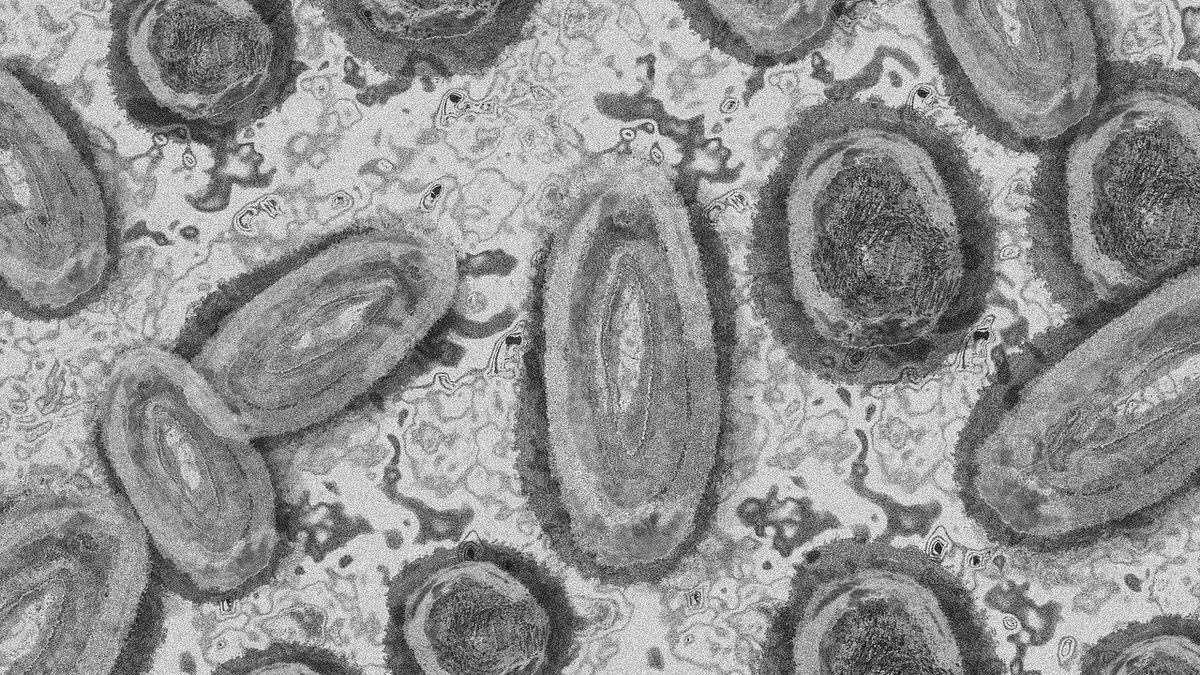

Sanidad detecta en Alicante el primer caso confirmado de viruela del mono en la Comunidad.